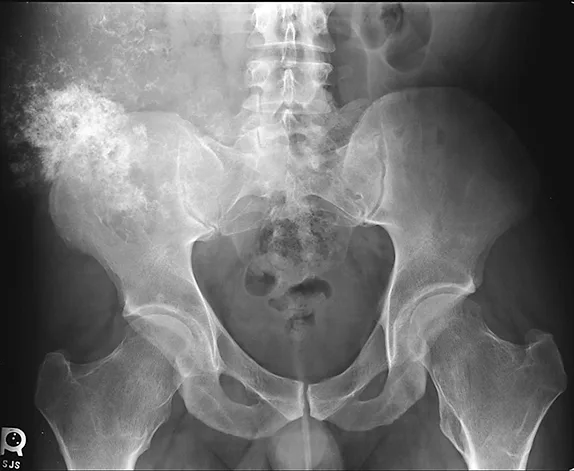

FIGURE 1

Anteroposterior radiograph showing a large mineralized mass with poorly defined margins and a wide zone of transition arising from the right ilium

Previously obtained anteroposterior pelvic radiographs (Figure 1) showed a large, poorly defined, mineralized lesion involving the right ilium. Because of the patients physical examination results, history of MHE, and radiographic findings, a secondary chondrosarcoma of the right ilium was suspected. Further diagnostic evaluation, including a CT scan (Figure 2) and MRI of the pelvis, were obtained to further characterize the lesion and begin surgical planning.